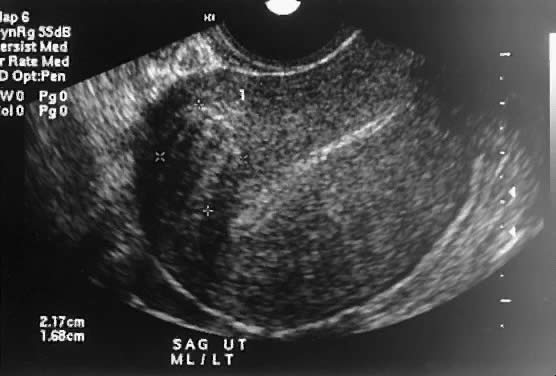

The typical problems presented by uterine leiomyomas have traditionally been evaluated by pelvic and abdominal examinations. Cantuaria and coworkers reported a strong correlation between bimanual examination and ultrasound examination with regard to determining the size of uterine myomas.10 The addition of ultrasonography (Fig. 3) and especially of magnetic resonance imaging (MRI) (Fig. 4) has increased the accuracy in the diagnosis and measurement of uterine leiomyomas. MRI often can differentiate adenomyosis from the leiomyoma. Radiologic studies are particularly important when the physical assessment is difficult, as in the case of morbid obesity, or when adnexal pathology cannot be excluded on physical examination. If there is any uncertainty about the diagnosis of uterine leiomyomas after radiologic studies, laparoscopy (Fig. 5), or laparotomy should be performed.

Fig. 3. Transvaginal ultrasound shows an intramural myoma.